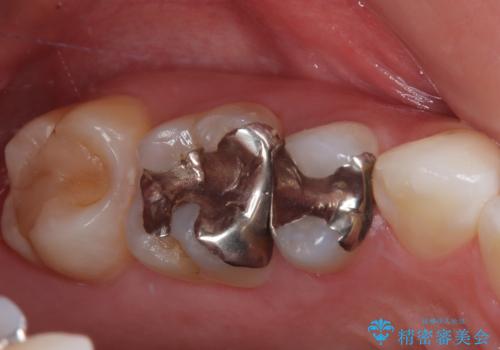

詰め物が外れかけてるのでやり替えたい セラミックインレー修復・フルジルコニアクラウン